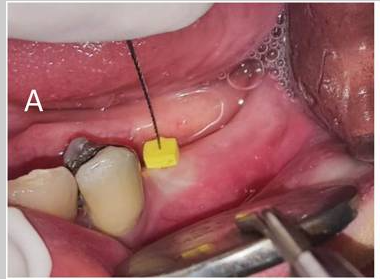

(A) Soft tissue thickness measurement (B) Keratinized gingiva measurement (C) Implant placement (D) Three months after implant placement and healing abutment closure